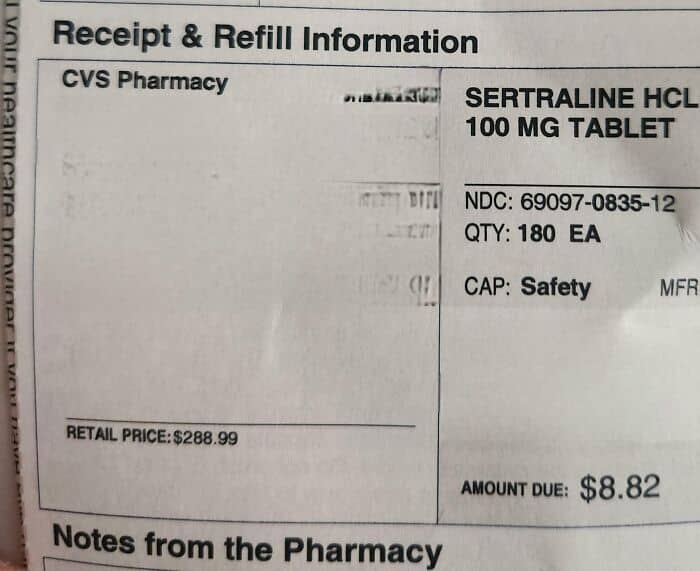

#92 The Retail Price Of My Antidepressant Before Insurance